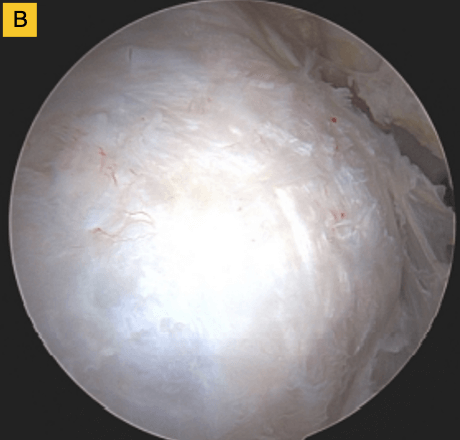

Down the road, this patient was having some bicipital pain, so we took the opportunity to look at the repair visually and performed a biceps tenodesis. You can see in this image, there's cabling of the fibers coming down onto the footprint and you can no longer see the scaffold… it’s been completely incorporated into the repair. For this patient, that was a pretty remarkable event.

(A) Tendon fibers can be seen inserting on to footprint in an organized fashion. Visible, prominent suture easily removed.

(B) BioBrace® well-synovialized and completely incorporated into the rotator cuff with new native tissue in and around the implant.